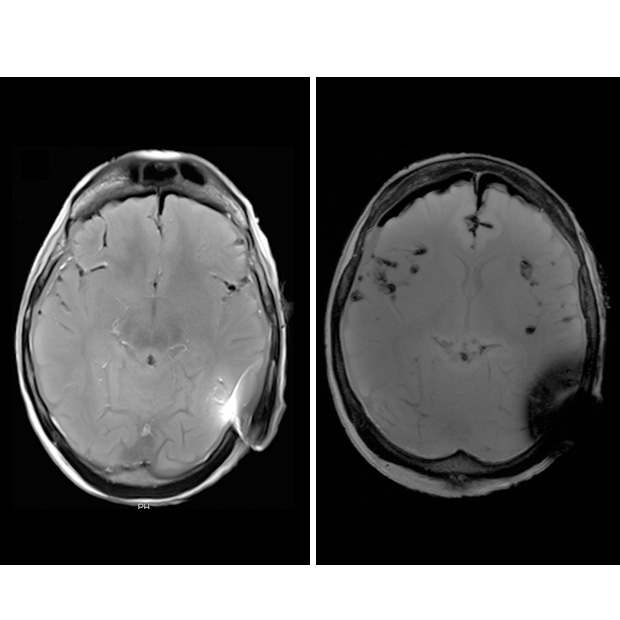

In fact, when asked radiologists stated that they could not make an accurate diagnosis from images scanned with 3 Tesla with the magnets in place because of the interference created by the magnets7 (see table below). This can be clearly seen on figure 1 of the MRI head scan, where the magnet creates artefacts. When this happens, the magnet has to be removed. For this reason, its ease of removal is an important factor when considering an implant.